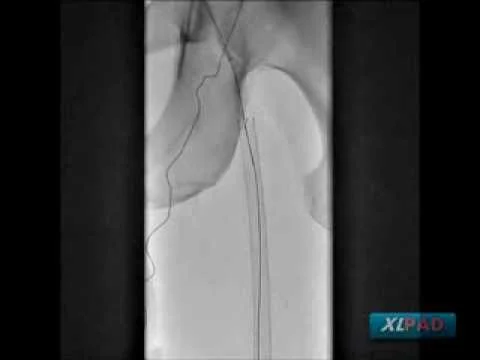

Proximal to Distal SFA CTO Treated with Viance